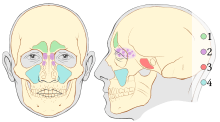

Outline of bones of face, showing position of air sinuses. Paranasal sinuses

Paranasal sinuses Nose diagram